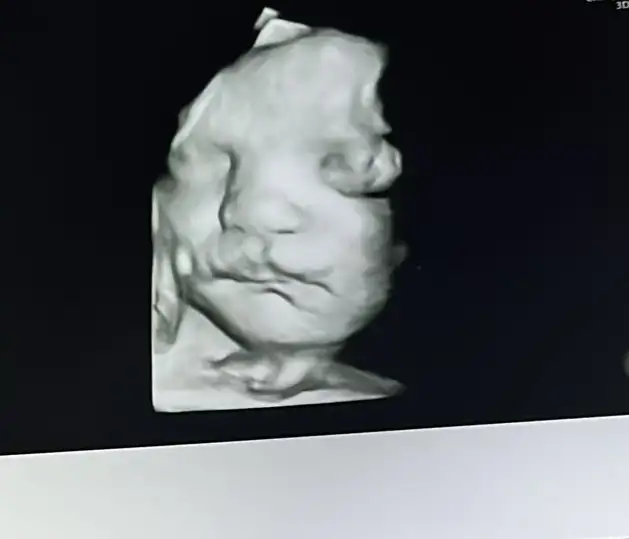

34+1 canım inşallah yüzünü gösterir senin kızçedeOy maşallah çok net çıkmış bende pazartesiyi iple çekiyorum doğru düzgün göstermedi bizim kız kendinibu arada kaç haftalıksın

Eki Görüntüle 3662548 Eki Görüntüle 3662549

Teyzoşlar bizim boyumuzda posumuzda günümüzle uyumluymuş

Hiçbir sıkıntı gözükmüyor dediya bakarmısınız şunun dudişine ısırcam yanaklarınıda yicemmm